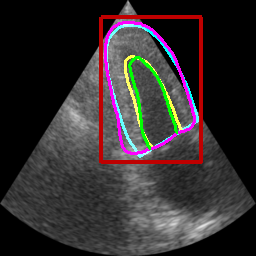

Table II displays the segmentation accuracy computed on the full dataset from patients having good and medium image quality ( patients) for the 4 algorithms described in section Sec. IV-D. Mean and standard deviation values for each metric were obtained from cross-validation on the 10 folds of the dataset. The values in bold correspond to the best scores for each metric. From these results, one can see that all the attention-based networks produced either the same, or better results than the baseline U-Net1, with AG-U-Net and LU-Net being the best performing models. Indeed, AG-U-Net obtained the overall best results for the segmentation of the LVEndo border ( value of mm and value of mm), leading to segmentation scores close but still higher than the intra-observer variability for this structure. The LU-Net-m5 approach obtained the best results for the segmentation of the LVEpi border ( value of mm and value of mm) and the lowest number of geometric outliers (%). Interestingly, these scores are either equivalent or lower than the intra-observer variability for this structure. It is also worth noting the robustness of the LU-Net model with respect to the choice of margin parameter, as margins of % and produce almost the same segmentation scores for all metrics. An illustration of the segmentation performance of the LU-Net-m5 network compared to the baseline U-Net1 model on three different cases is provided in Fig. 2.